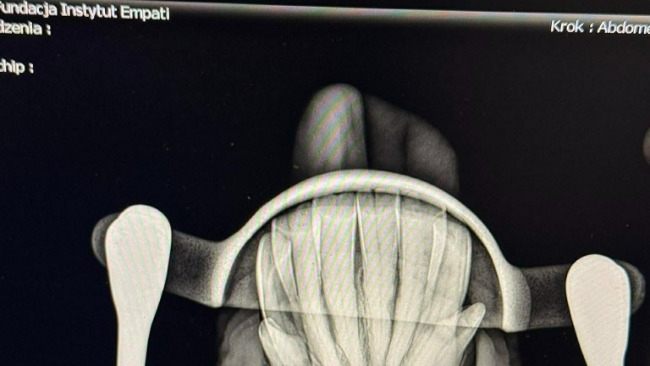

Black od razu po przyjeździe trafił pod opiekę weterynarza, bo stan jego siekaczy nie wyglądał już tak dobrze, jak on sam. Diagnoza: EORTH. Choroba o tajemniczej nazwie, która niewiele mówi, a nie wyobrażamy sobie jak wielki ból oznacza.

EORTH najczęściej dotyczy siekaczy i kłów. Polega na rozpuszczaniu korzenia zęba oraz nadmiernym odkładaniu się cementu — jednej z warstw budujących ząb. To bardzo bolesne schorzenie, a jedyną metodą leczenia jest usunięcie chorych zębów.

I właśnie to musiało się stać.

Na szczęście konie potrafią zadziwiająco dobrze odnaleźć się także bez siekaczy. Zębodoły u Blacka po tym trudnym zabiegu goją się bardzo dobrze, a on sam zdaje się już zostawiać ból za sobą.